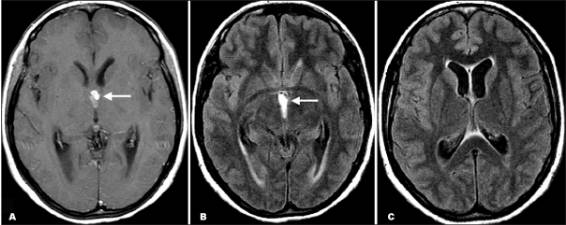

Sau khi thăm khám và điều tra bệnh sử, chụp cắt lớp vi tính có hoặc không có bơm thuốc cản quang đường tĩnh mạch là bước đầu tiên trong chẩn đoán các ca bệnh nghi ngờ ATSL thần kinh. CT não có hoặc không có thuốc cản quan sẽ cho thấy hình ảnh các tổn thương điển hình của ATSL đường kính nhỏ hơn 20mm và không có hình ảnh phản đứng giữa (no midline shift) là hình ảnh gợi ý cao cho thể ATTSL thần kinh (neurocysticercosis). Phần scolex, hoặc phần giác hút của ấu trùng cũng có thể nhìn thấy; đây là đặc trưng bệnh của ATSL thể thần kinh.

Hình 2. trên hình ảnh CT có nang của ATTSL thể thần kinh trong nhu mo não đặc | Hình 3. hình ảnh cộng hưởng từ cho thấy các nang của ATSL thể thần kinh trong nhu mô |

Số lượng, kích thước và vị trí có nang xuất hiện cũng như giai đoạn chu kỳ của nang sán, có thể xác định và có thể tác động đến việc quyết định điều trị. Các nang là các hình ảnh tổng thương dạng điểm có thể phát triển và tồn tại được, nang không bị thoái hóa. Các tổn thương dạng nang chỉ ra biến tính hoặc thoái hóa có một vài phản ứng viêm bao quanh. Cuối cùng, các nang hình thành calci hóa là một bằng chứng các nang đã tồn tại lâu có thể đã chết. Chăm sóc phải được tiến hành khi có thể còn nghĩ đến nhiều nguyên nhân khác (lao, bệnh ký sinh trùng khác, di căn từ nơi khác đến, hoặc ung thư nguyên phát của não hoặc hình ảnh abces não) khi một tổn thương tìm thấy trên phim chụp cắt lớp.

Hình ảnh trên phim chụp cộng hưởng từ cũng là công cụ hữu ích để chẩn đoán ATSL thể thần kinh và có thể tốt hơn cả chụp cắt lớp CT để phát hiện các thương tổn trong não tủy, trong cuống não, trong não thất. Việc áp dụng nó nên cân nhắc khi CT không chẩn đoán ra. CT và siêu âm là rất nhạy để phát hiện các tổn thương ATSL tại mắt và hệ cơ xương.